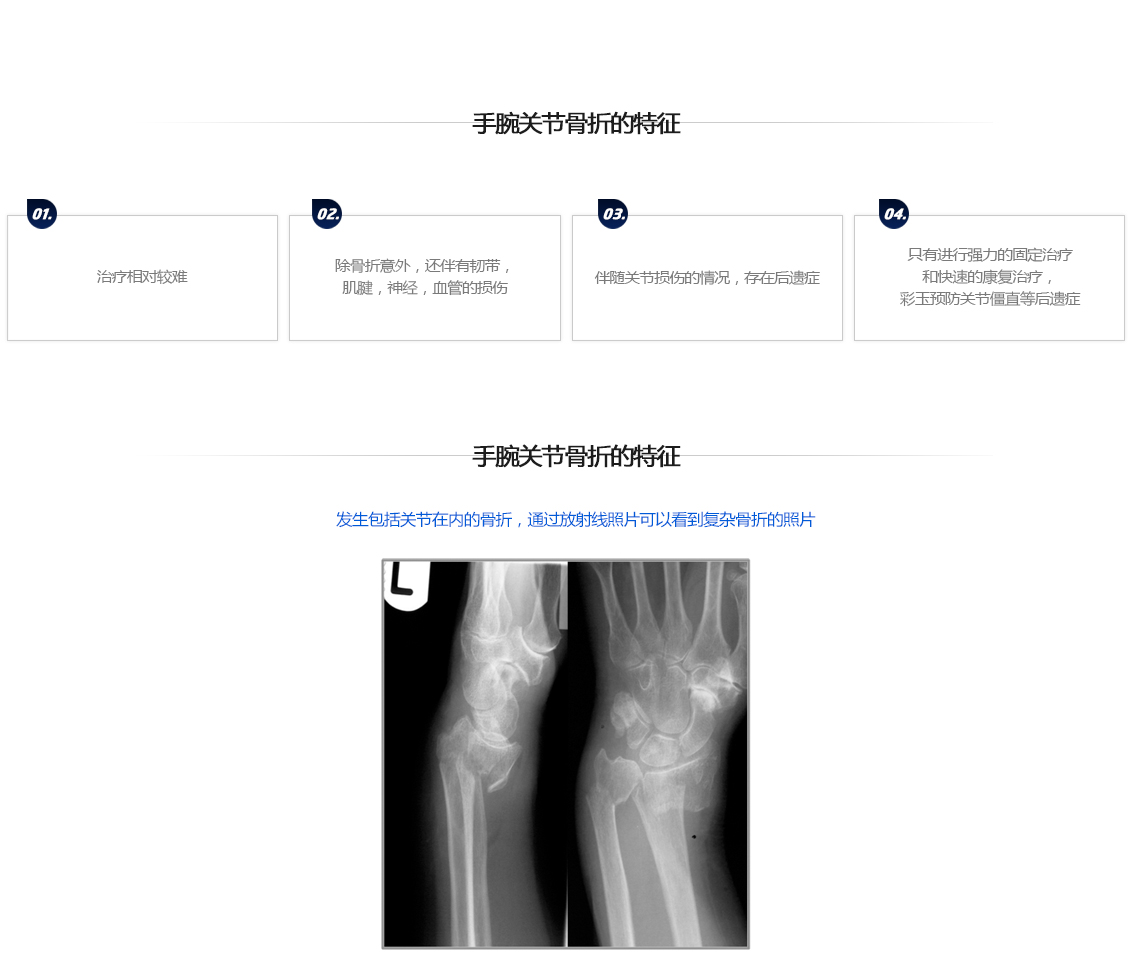

手腕关节骨折